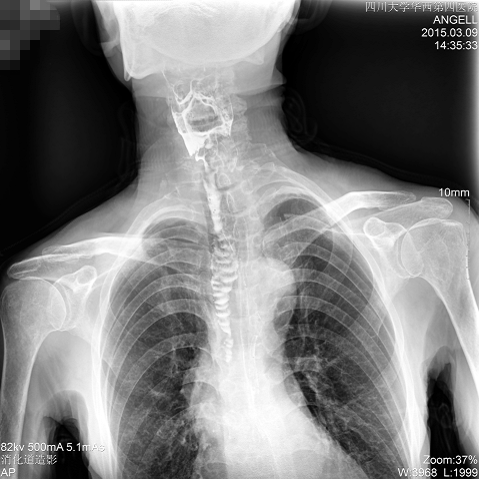

如下圖所示:該患者因吞咽時感到很難受,進(jìn)食時也經(jīng)常咳嗽故就醫(yī)診斷。使用多功能dr為病人進(jìn)行消化道造影診斷,要求他吞鋇后發(fā)現(xiàn),食道各段通過順利,形態(tài)規(guī)則,雙側(cè)梨狀窩不對稱左側(cè)稍淺,多次吞咽動作后,仍見鋇劑滯留,并見鋇劑進(jìn)入氣管,屬于會厭征陽性。會厭功能紊亂,鋇劑進(jìn)入了氣管。

圖為斜位:通過動態(tài)影像可以清楚看到鋇劑進(jìn)入了支氣管道

通過多功能dr可以診斷該病人的癥狀為會厭功能紊亂,鋇劑進(jìn)入到了氣管。而在動態(tài)透視下可以清晰的觀察到鋇劑從何處進(jìn)入氣管,可清晰顯示食管粘膜結(jié)構(gòu)。使用多功能dr其獨特的視頻采集技術(shù),可實時保存視頻并能實現(xiàn)900萬像素實時點片,才能獲取這樣清晰的病灶點。而常規(guī)dr只能拍攝靜態(tài)片,且成像效果大打折扣,因此較難確診病灶。